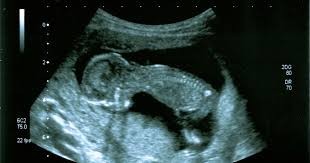

La Cámara de Diputados aprobó en su sesión de hoy y dio sanción definitiva, a un proyecto de ley remitido en revisión, a través del cual se incorpora con carácter obligatorio y como práctica rutinaria de control en el territorio de la Provincia de Catamarca, la realización de ecografías fetales con evaluación cardíaca y eco doppler color a todas las embarazadas con edad gestacional entre las veinte (20) y veinticuatro (24) semanas, especialmente en el periodo gestacional comprendido en la semana veintidós (22).

La iniciativa parlamentaria pertenece a la diputada Juana Fernandez. En la ocasión estuvieron presentes integrantes de la organización no gubernamental Corazón con Augeritos, con quienes la legisladora trabajó el proyecto. La diputada agradeció el acompañamiento de la misma, de profesionales que aportaron al proyecto, a la comisión que le dio luz verde y “la predisposición y valor de lo que significan patologías como estas para tener una ley que mejorará la calidad de vida de las personas que padecen esta enfermedad”.